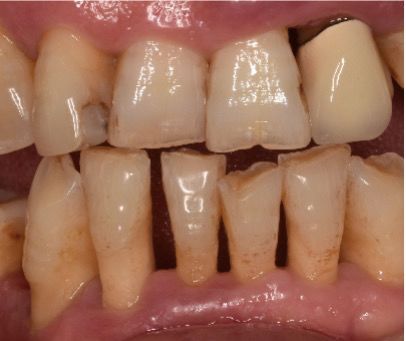

左边是洗牙前的牙齿。中间阴影的部分,是牙间隙,也就是我们所说的牙缝。

右边是洗牙后的牙齿。可以看到,阴影的部分的确增大了。这是为什么呢?

因为这些患者的牙齿,由于长期清理不到位,患了牙周炎,牙龈也因为发炎而变得肿胀起来,牙龈的位置也随之变高了。洗完牙后,一方面牙齿间隙中原有牙结石的空间释放出来了,另一方面,牙龈也消肿了,退缩到了正常的位置,释放出了一点空间,两者一结合,就出现了牙缝变大的结果。

所以,洗牙并不是造成牙缝变大的根本原因。根本原因,应该是牙周炎。

牙周炎可表现为牙床退缩、牙缝变大和牙齿移位